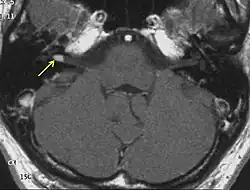

На МРТ выявляется ровный контур опухоли и по её периферии полоска сигнала так называемой «ликворной щели», деформация мозжечка и ствола головного мозга. При распространении невриномы во внутренний слуховой проход внекананальная её часть имеет вид «свисающей капли»[30].

Приблизительно 2/3 неврином выглядят гипоинтенсивными, а одна треть изоинтенсивными на Т1-взвешенных томограммах. На Т2-взвешенных томограммах невриномы характеризуются повышением сигнала, степень которого варьирует. Участки гетерогенно изменённого сигнала (вследствие образования кист) характерны для новообразований больших размеров (как правило, более 3 см). Все невриномы интенсивно накапливают контрастные вещества, более чем в 70 % случаев их накопление гетерогенно[30].